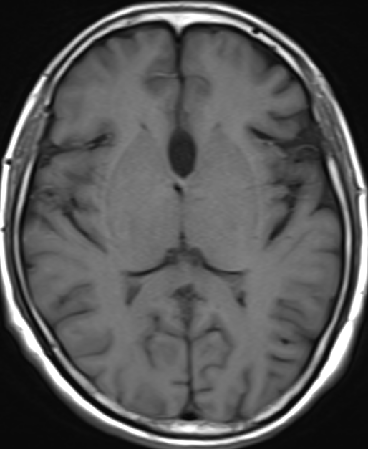

2013-5-16 MRI